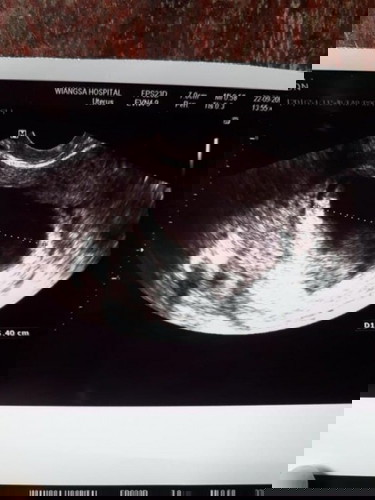

แบบนี้จะใช่ท้องลมไหมค่ะ

ทุกคนค่ะ แบบนี้ใช่ท้องลมรึเปล่าค่ะ พอดีไปซาวที่รพ.มาวันนี้ หมอบอกไม่มีเด็ก แต่แม่เห่นคล้ายๆว่าเป็นเด็ก ทุกคนช่วยดูหน่อยค่ะ หรือว่าแม่คิดไปเอง

หมอน่าจะเชี่ยวชาญค่ะแม่